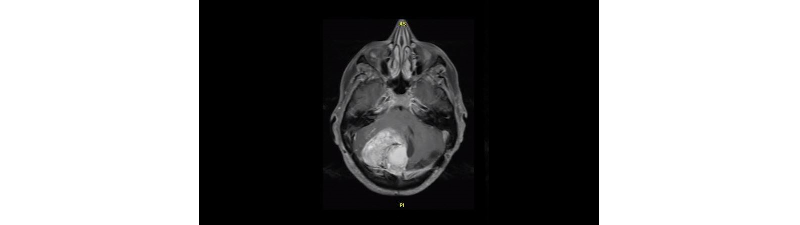

Making inoperable brain tumors treatable

Treatment of brain tumors is often challenging and risky due to their complex nature and proximity to sensitive tissue. Improved visualization and planning allow for a better understanding of the tumor before surgery begins.

Interoperative MRI shows brain activity during surgery to guide surgeons.

Fluorescence-Guided Surgery shows where the tumor is located in the brain beyond what can be seen with the naked eye.

Additional diagnostic techniques provide insight into tumor firmness, adhesion to other tissue, and ways to save surrounding, healthy tissue.